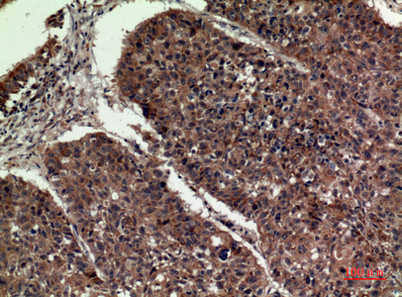

Product name: ApoA-I rabbit pAb

Dilutions: Western Blot: 1/500 - 1/2000. IHC-p: 1/100-1/300. ELISA: 1/20000. Not yet tested in other applications.

Immunogen: The antiserum was produced against synthesized peptide derived from the Internal region of human APOA1. AA range:81-130